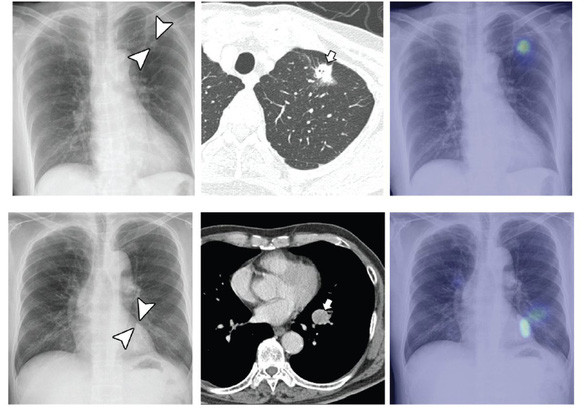

Chẩn đoán hình ảnh chụp tia X phần ngực bằng thuật toán DLAD - Ảnh: Twitter của ERICTOPOL

Thuật toán đầu tiên giúp giải quyết nhiệm vụ phân loại hình ảnh với hiệu quả vượt trội. Mùa thu năm 2018, các nhà nghiên cứu tại Bệnh viện ĐH quốc gia Seoul và CĐ Y khoa Hàn Quốc đã phát triển ra thuật toán có tên DLAD để phân tích các ảnh chụp tia X phần ngực và phát hiện những khối u phát triển bất thường có thể là tín hiệu ung thư.

Hiệu quả chẩn đoán hình ảnh của thuật toán này đã được so sánh với khả năng phát hiện bệnh của nhiều bác sĩ khi cùng xem xét các ảnh chụp X-quang giống nhau và ứng dụng DLAD đã làm tốt hơn 17/18 bác sĩ .